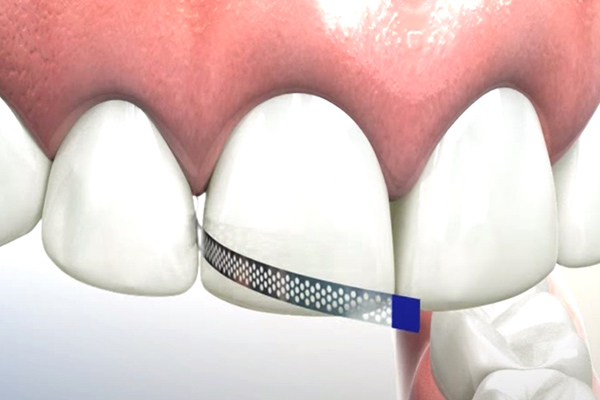

歯を最小限の範囲で削るディスキング(I.P.R)

歯の表面(エナメル質)を少しだけ削ることで、歯を動かすスペースを確保する治療法です。エナメル質は2~3mmの厚みがあり、その1/5~1/10(0.1mm~0.3mm)程を削ります。元々、歯が咬み合う部分のエナメル質は年齢とともに消耗し、一生かかって2mm程度削れてしまうと言われております。歯の接触部分は消耗することがないのでそのままの厚みが保たれており、矯正治療で削る量は生理的に消耗する量に比べると、ほんのわずかとなります。100年以上前から使用されている安全性が確立された方法で、虫歯などの歯に対するリスクはほぼゼロの治療法ですのでご安心ください。